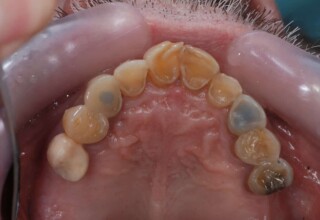

Εκτεταμένη αποκατάσταση με στεφάνες(θήκες) σχεδόν σε όλα τα δόντια λόγω εκτεταμένων αποτριβών, παλαιών αποκαταστάσεων, οπισθίων απονευρώσεων και αισθητικών προβλημάτων. Ο ασθενής(60 ετών) παρουσίαζε έντονο βρυγμό (τρίξιμο δοντιών) που δεν είχε αντιμετωπίσει ποτέ, με αποτέλεσμα μεγάλες αποτριβές που απειλούσαν την ακεραιότητα των οπισθίων δοντιών. Οι ανασυστάσεις(σφραγίσματα) των δοντιών έγιναν κυρίως με συγκολλούμενα ρητινώδη υλικά και τρεις χυτούς άξονες ψευδοκολοβώματα. Τοποθετήθηκαν προσωρινές στεφάνες όπου εκτιμήθηκε το επιθυμητό μέγεθος, το σχήμα και η θέση των δοντιών πριν κατασκευαστούν οι τελικές μόνιμες στεφάνες.